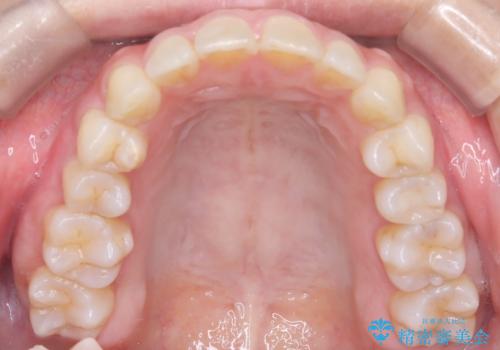

【インビザライン】前歯の凸凹を治したい

- 前歯の凸凹を主訴に来院されました。

臼歯部の遠心移動を行いながらスペースを作り、インビザラインにて前歯をきれいに並べることができました。

今回の治療計画では臼歯部の遠心移動とIPRを行っています。